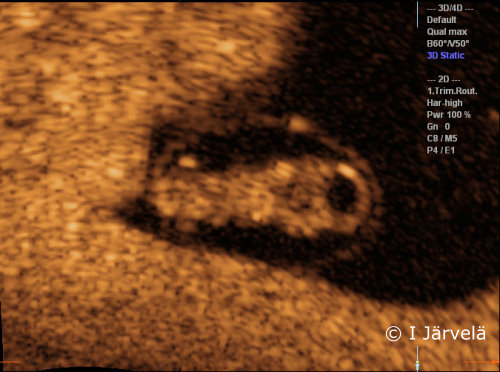

Pregnancy Week 7 (Ultrasound Scan)

Pregnancy week 7 (ultrasound scan). The embryo in the amnion sac (AS) in the 7th week of pregnancy. The fourth cerebral ventricle in the fetal head, as well as the limb buds are detectable.

Picture: Ilkka Järvelä; text: Dimitrios Scordas